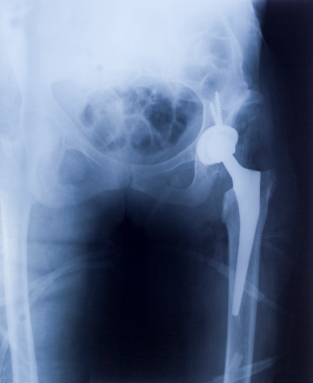

Having hip implant surgery is challenging enough—the recovery period, the high costs even with good insurance, and of course the innate risk of surgery itself. Now imagine if the hip implant was defective. This is exactly what many Stryker hip implant patients are facing, finding out after their surgery, notwithstanding pain and suffering, that their device may have been defective.

Technically not a metal-on-metal (MOM) hip implant, the Stryker system does have MOM components as well as the same complications. Fretting, erosion and metal poisoning are much more common than what many consider as acceptable. At the core of the growing hip implant multidistrict litigation (MDL) is the allegation that Stryker knew about the risks of hip implant failure but chose not to warn anyone about them.

“On January 28, 2011, Neysa Bennett had a right hip surgery at which time a Stryker Rejuvenate Modular Hip was installed,” the Bennett’s hip implant lawsuit states. “At the time Neysa Bennett had the Stryker Rejuvenate Modular Hip System implanted into her body, she did not know that the system was dangerously defective in that the junction of the stem and neck components of the System fret, galvanize, and corrode in a manner that results in implant failure and the release of toxic heavy metals into the body.”

“Following Neysa Bennett’s hip replacement surgery, on or about July 4, 2012, Defendants initiated a voluntary recall of the Stryker Rejuvenate Modular Hip System due to the potential for fretting and/or corrosion at or about the modular-neck junction. Prior to the aforesaid recall on July 4, 2012, Neysa Bennett and Thomas Bennett had no knowledge that the Stryker Modular Hip System or any of its component parts was defective. This fretting and corrosion resulted in adverse local tissue reactions manifesting with pain and/or swelling, as well as tissue necrosis, metallosis, adverse soft tissue reaction, and pseudotumor formation,” the Stryker hip lawsuit states.